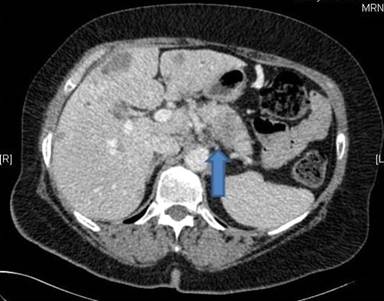

In January 2011 a 69-year-old female patient was admitted to our hospital due to persisting abdominal pain and elevated liver enzymes in the serum. Based on CT-scans (Figures 1 and 2) and laboratory diagnostics, adenocarcinoma of the pancreatic tail with multiple liver metastases was diagnosed. This diagnosis was confirmed histologically by biopsy of one of the liver metastases revealing poorly differentiated adenocarcinoma (Figure 3). Because of the clear constellation of diagnostic findings immunohistochemistry was dispensable. In our interdisciplinary tumor conference palliative chemotherapy was suggested. Because of the patients’ excellent performance status (ECOG 0) a first line therapy including folic acid, fluorouracil, oxaliplatin and irinotecan (FOLFIRINOX) was initiated in February 2011. In follow up staging CT scans showed significant shrinkage of the liver metastases and of the primary tumor, while serum CA 19-9 decreased concomitantly (Figure 4). After 2 years of chemotherapy, in February 2013, liver metastases could hardly be detected anymore, whereas the primary tumor in the pancreatic tail was still detectable and suspicious of residual cancer tissue. Thus, chemotherapy with FOLFIRINOX was continued. Subsequently, the lesion in the pancreatic tail stayed exactly the same size over another year of chemotherapy, while liver metastases did not recur as long as FOLFIRINOX was administered. In April 2014 we additionally performed an FDG-PET-CT-scan to find out whether the primary lesion in the pancreatic tail was still representing vital tumor tissue. Neither in the liver nor in the pancreatic tail FDG-uptake was increased (Figures 5, 6). Thus, we paused chemotherapy for 12 weeks and performed another CT-scan in August 2014 revealing a single metastasis in segment IVb of the liver. This metastasis was treated by radio frequency ablation (RFA). Six weeks later another CT-scan showed no sign of vital tumor tissue in the pancreas or the liver or elsewhere in our patient.

Figure 1. CT-scan of our patient in February 2011: tumor in pancreatic tail-region marked with the blue arrow. |